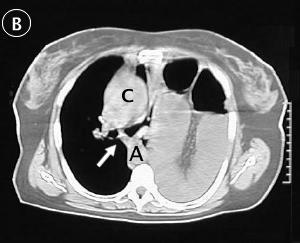

Corte Tomográfico B

Flecha: carina, observe el desplazamiento del mediastino hacia la derecha.

c: corazón desplazado a la derecha.

A: Aorta desplazada